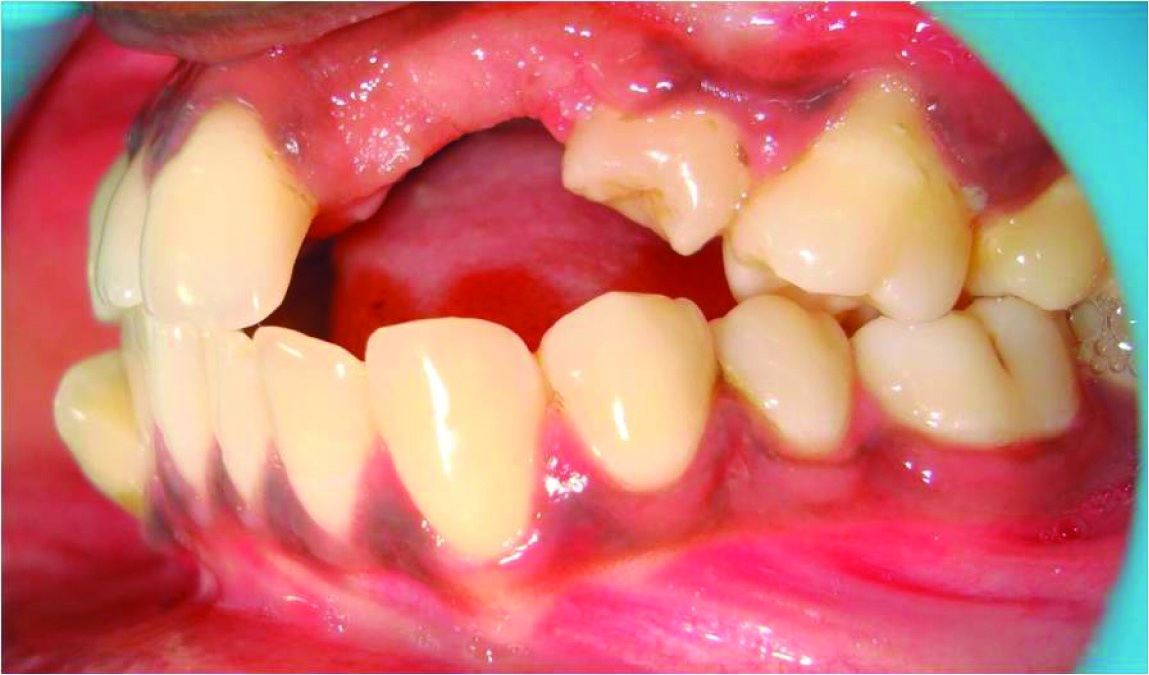

A 21-year-old female patient came to the Department of Prosthodontics and Implantology, Thai Moogambigai Dental College and Hospital, Chennai, India with a complaint of unaesthetic appearance due to missing upper front tooth for which she wanted fixed replacement of her missing front teeth. Patient gave a history of trauma when she was four years of age which was not attended immediately. The patient developed a swelling after three months of injury following which 61,62,63,64 were extracted and were not replaced.

On clinical examination there was congenital absence of 21,22,–23,24 and severe midline shift of right side anterior teeth towards the left side. The edentulous ridge in relation to 21,22,23,24 appeared narrow and resorbed. Due to the missing anterior teeth, 25 were also rotated towards the edentulous space. Crowding of the lower anterior teeth was noted [Table/Fig-1].

The patient’s ridge defect was classified based on Seibert’s nomenclature [1] and Struder et al., quantitative assessment of bone defects [2]. Intraoral clinical picture of the patient showed that there was loss of residual ridge horizontally as well as vertically at the edentulous space in the maxillary arch and hence it was categorized as Seibert’s Class III type of ridge defect, thereby clinically making the implant placement a questionable procedure. The patient was not willing for surgical bone grafting along with implant placement. A conventional fixed partial denture was also not possible due to the severity of the bone defect.